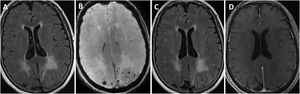

All patients underwent head CT scans at baseline, with 6 presenting subcortical hypodensities. Brain MRI scans were also performed in all patients during the first days after admission; results are shown in Table 3. All patients presented extensive unilateral (4) or bilateral (3) subcortical hyperintensities in the FLAIR sequence, with a clear predominance in posterior regions. Other relevant findings were lobar microbleeds (7), cortical superficial siderosis (4), and leptomeningeal contrast uptake in the region adjacent to the subcortical hyperintensity (6). No patient presented deep microbleeds. Fig. 1 presents the main neuroimaging findings from one of the patients.

Brain MRI findings from patient 6.

The patient was an 83-year-old woman with acute symptoms of disorientation, confusion, and seizures. Brain MRI shows bilateral involvement of parietal white matter, predominantly affecting the left side (A). Susceptibility-weighted sequences (B) revealed multiple cortical microbleeds at the posterior edge of both parietal lobes; leptomeningeal contrast uptake within the sulci was more clearly identified on FLAIR sequences (C) than on post-contrast T1-weighted sequences (D).